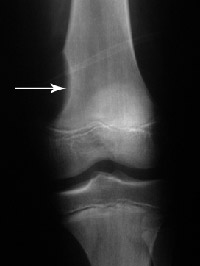

Your doctor will probably obtain X-rays for further information. Each type of tumor can exhibit different characteristics on X-ray. Some dissolve bone or make a hole in the bone. Some cause an extra formation of bone. Some can result in a mixture of these findings. In other cases, it may be difficult to tell what kind of tumor is involved, and additional imaging studies such as MRI (magnetic resonance imaging) or CT (computed tomography) could be called for.